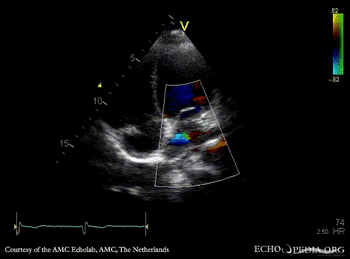

E00580.gif E00581.gif

PSAX with Color Doppler A3CH with Color Doppler